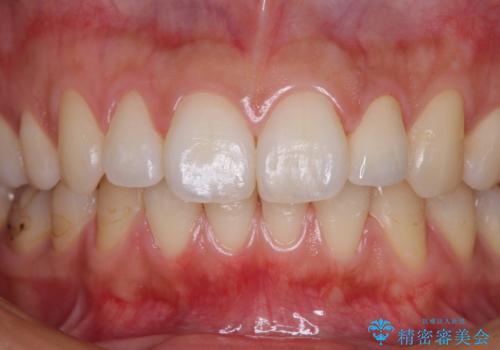

根管治療を行い、その後オールセラミッククラウンにて補綴治療を行うこととしました。

- 治療費の目安: 26万円(税込) 内訳:根管治療(イニシャルケース) ¥88,000、仮歯 ¥11,000、ファイバーコア ¥22,000、クラウン ¥139,000費用は治療当時の料金となります

根管治療後速やかに痛みが消退し、6ヶ月後のレントゲン写真では、根尖部の病変がほぼなくなっていることが分かりました。